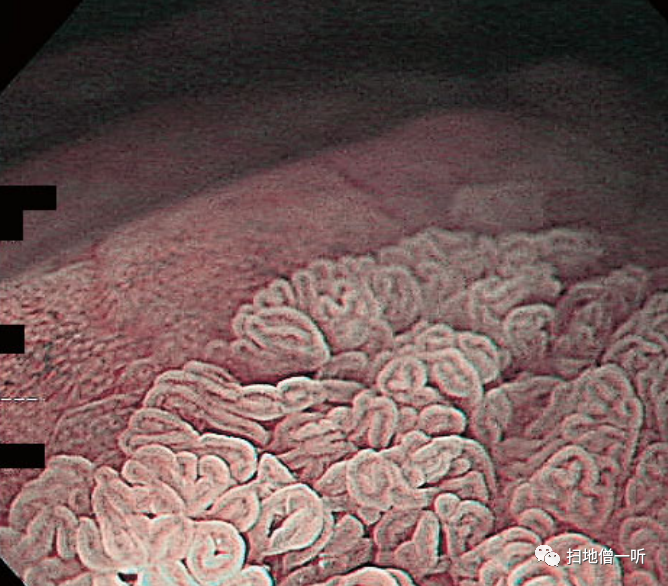

【铺路石样粘膜】

患者60多岁,男性。胃体上部的铺路石样粘膜所见。

▲组织学上发现壁细胞肿大,空泡变性。

PPI直接作用于胃壁细胞,在抑制胃酸分泌的同时,诱导胃壁细胞进入非生理状态。在病理组织学上,壁细胞肿大膨化,内腔侧呈锯齿状变化。这种病情在病理组织学上被称为PCP(parietal cell protrusion)。此外,在壁细胞中也可以看到增生性变化。上述变化并不反映特定的内镜观察结果,但在胃体部发现了铺路石样粘膜。

▲在放大观察中,观察到了条纹状的微细粘膜图案。

▲在病理组织学上,表层的腺窝上皮出现了增生性变化。